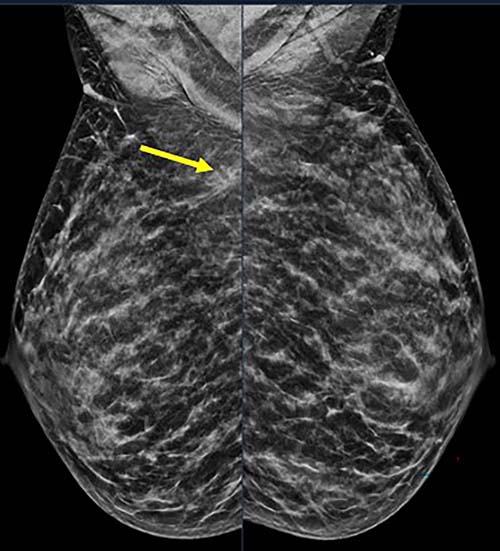

Figure 1. 40-year-old patient presents for routine screening. Family history of paternal grandmother age 55. Extremely dense breast tissue is noted on mammography right and left craniocaudal (taken from the top of the breast) view.

Figure 2. 40-year-old patient presents for routine screening. Family history of paternal grandmother age 55. Extremely dense breast tissue is noted on mammography right and left mediolateral oblique (side angle) view. In addition, an area of architectural distortion is seen at the posterior right breast on right view (see arrow).